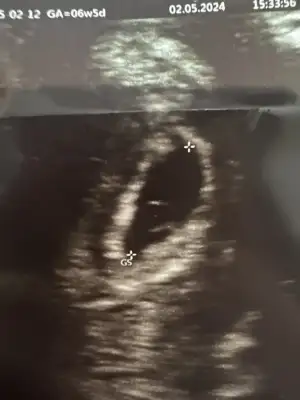

Aha da şu yani belli sende de 😅

Kızlar benim kesenin içinde birsey görüyor musunuz peki 🥹🧡

Eklentiler

• 680221E5-A673-45DA-98A9-1629644C9D13.webp

680221E5-A673-45DA-98A9-1629644C9D13.webp

89,7 KB · Görüntüleme: 83